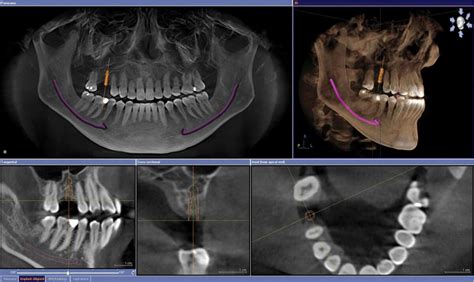

Rayos X CBCT

Los equipos de rayos X CDBC (Cefalometría 3D y 2D con Bomba de Cono) representan una avanzada tecnología en el ámbito de la radiología dental, especialmente en el campo de la ortodoncia y la cirugía maxilofacial. Estos equipos ofrecen capacidades tanto en 2D como en 3D, lo que los convierte en herramientas versátiles y completas para el diagnóstico y planificación de tratamientos dentales.

La funcionalidad de cefalometría 3D permite obtener imágenes tridimensionales de la cabeza y el cráneo, proporcionando a los profesionales una visión más detallada y precisa de las estructuras faciales. Esto resulta especialmente valioso en el diseño de tratamientos ortodónticos y cirugías maxilofaciales, ya que permite evaluar las relaciones óseas y dentales desde múltiples ángulos.

La inclusión de una bomba de cono en estos equipos proporciona una mayor precisión en la focalización del haz de rayos X, permitiendo una radiación más enfocada y reduciendo la exposición a tejidos circundantes. Esto contribuye a mejorar la seguridad y minimizar la dosis de radiación para el paciente, un aspecto fundamental en la práctica odontológica moderna.

Los rayos X CDBC con capacidades de cefalometría 3D y 2D ofrecen a los profesionales de la odontología herramientas avanzadas para el diagnóstico y la planificación de tratamientos ortodónticos y maxilofaciales. La combinación de estas tecnologías proporciona una visión integral de la anatomía facial, permitiendo una toma de decisiones más informada y un enfoque más preciso en los procedimientos clínicos.

- RAY: Equipos de Rayos X 3D Panorámica CBCT con y sin teleradiografía (cefalostato). Ofrecen enfoque de movimiento adaptable y eliminación de ruido.